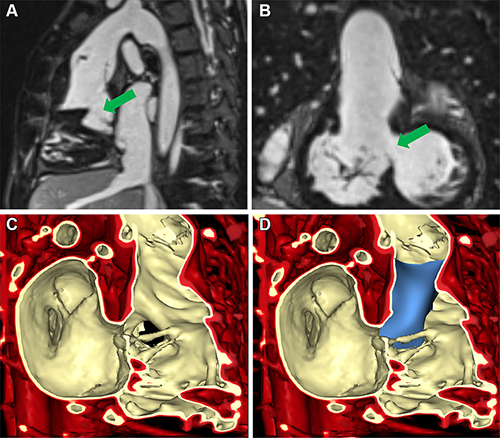

Figure 2. Volume rendering of ferumoxytol-enhanced inversion-recovery fast low-angle shot imaging from cardiac MRI in a 6-year-old female patient with a right ventricle to aorta and malalignment ventricular septal defect (VSD) (patient 2) to inform planning of biventricular repair. (A) Sagittal and (B) coronal views demonstrate VSD (green arrow). (C) Volume rendering of cardiac MRI. (D) Volume rendering with baffle placement using SlicerHeart.

Video 5. Imaging of a 6-year-old female with a malignment VSD, right ventricle to aorta, and pulmonary atresia (patient 2). Ferumoxytol contrast enhanced inversion recovery gradient echo imaging demonstrates the intracardiac anatomy and highlights the VSD in the axial, coronal and sagittal views. Volume rendering of this imaging results in a 3D demonstration of the VSD from the right ventricular and left ventricular views. Measurements displayed were performed using multiplane reconstruction as well as specific views in the 3D image. Finally, a virtual baffle is applied over the volume rendering to demonstrate feasible surgical strategies for pre-procedural planning.